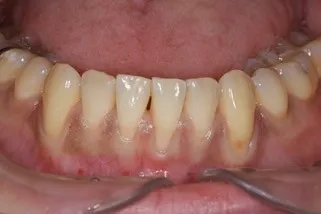

歯肉退縮の形成

治療名

根面被覆治療

治療回数・期間

1回(後日抜糸を行います)

副作用・リスク

歯肉が下がってしまったすべてを回復できるわけではなく、どの程度回復できるかは状態により異なります。

料金

¥110,000(税込)